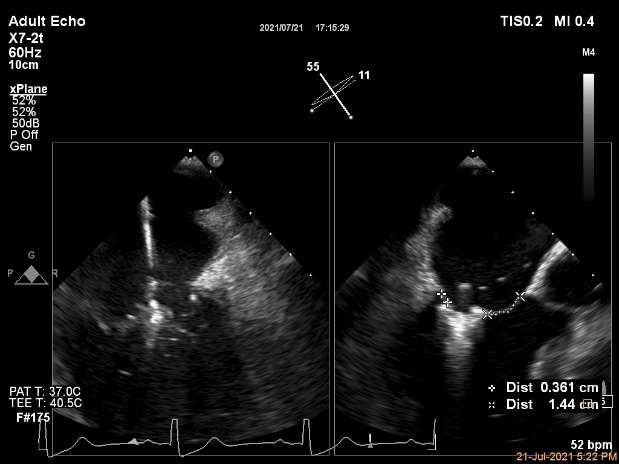

术中超声引导:

确定房间隔穿刺点:靠后

穿刺点高度测量:4.14cm

2D视图下测量大鞘长度2.2cm

2D视图下建立trajectory

3D视图打开夹子

3D视图下调Rotate,定位2区

X-plane:下夹子尝试捕获2区

夹子逐渐夹闭后,2区返流逐渐减少

3D:测量前叶长21.2mm,后叶长10.2mm

X-plane:计算前叶捕获长度6.8mm,后叶捕获长度6.5mm

夹子放置后二尖瓣口平均跨瓣压差:3mmHg

肺静脉血流频谱恢复正常

3D视图下观察二尖瓣双孔形态

3D-color:残余少量返流